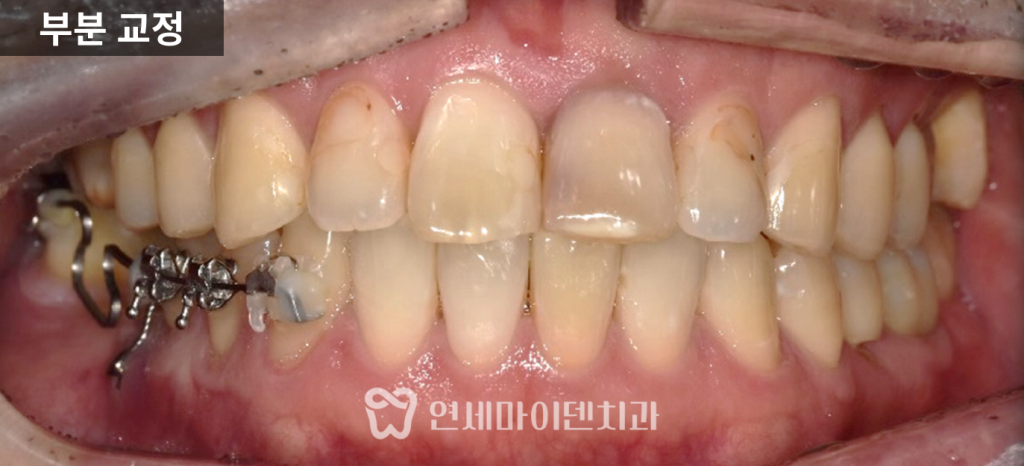

부분 교정 7개월차 경과

7개월 차에는 쓰러졌던 7번 어금니가

거의 정상 각도로 회복되었으며,

6번 어금니 임플란트를 위한 공간이 충분히 확보되었습니다.

다만 오랜 기간 기울어져 있던 탓에 치근(뿌리)까지

완전히 이동시키는 것은 비효율적이었기 때문에,

기능적으로 무리가 없는 선에서 교정을 마무리하였습니다.

이 시점에서 이미 임플란트 식립이 가능한

안정적인 공간이 확보되었으며,

교합(물림)도 정상 범위 내에서 조정되었습니다.